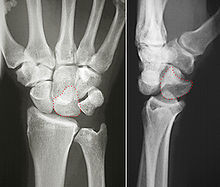

Perilunar dislocation as seen on x-ray.

The lunate bone is the most frequently dislocated carpal bone.